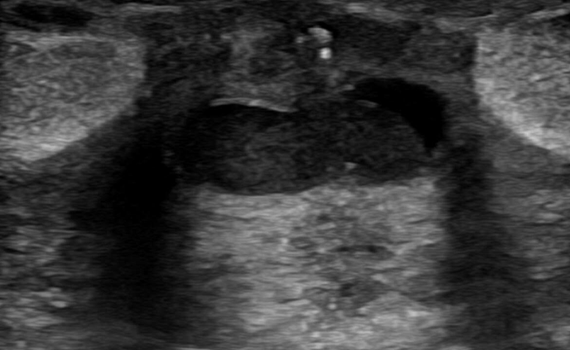

¿Cuál es su diagnóstico?

Imagen de la semana